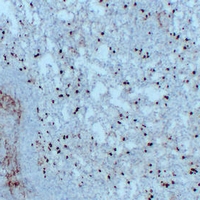

IHC (Immunohistochemistry)

(Immunohistochemical analysis of CD14 staining in human spleen formalin fixed paraffin embedded tissue section. The section was pre-treated using heat mediated antigen retrieval with sodium citrate buffer (pH 6.0). The section was then incubated with the antibody at room temperature and detected using an HRP conjugated compact polymer system. DAB was used as the chromogen. The section was then counterstained with haematoxylin and mounted with DPX.)